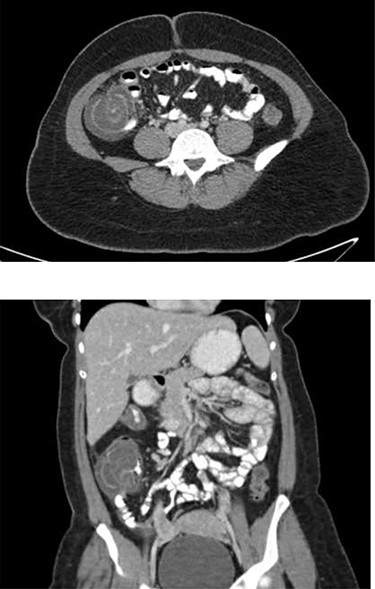

A 25-year-old female with a history of hypertension and peripartum pericarditis 2 years prior (recent echocardiogram normal) presented to the emergency department (ED) with a sore throat, fevers and myalgias. She had no diarrhea, constipation or blood in stool noted. On exam she had a fever to 38.7°C and tachycardia, and normal oxygen saturations on room air. Complete blood cell count and basic metabolic panel were not performed. She tested positive for COVID-19 infection via nasopharyngeal polymerase chain reaction (PCR), and was discharged home. She presented 4 days later to the ED with 1 day of intermittent severe cramping abdominal pain located in her right lower quadrant. She reported new onset nausea, vomiting and bright red blood in the stool. She was febrile to 38.2°C, heart rate was 92 bpm, blood pressure was 104/62 mm Hg and respiratory rate was 18 breaths per minute. On exam she was mildly distended with minimal abdominal tenderness. She had a white blood cell count of 14.1 × 103/μl with 85.7% segmented neutrophils, platelets of 344 THOU/μl and hemoglobin of 14.0 g/dl. Metabolic panel was within normal limits (WNL) with creatinine 0.73 mg/dl. Blood glucose was 104 mg/dl. Liver function tests were WNL. Computed tomography (CT) of the abdomen and pelvis with oral and intravenous (IV) contrast was performed, which revealed mild dilation of small bowel and decompressed distal colon with transition point related to ileocolic intussusception with segmental thickening of the cecum and proximal ascending colon, possible cecal mass and trace free fluid (Fig. 1). COVID-19 nasopharyngeal PCR was repeated per hospital policy and was again positive.

Representative axial (top) and coronal (bottom) images from patient’ s CT abdomen/pelvis with PO and IV contrast demonstrating cecal thickening and ileocolic intussusception.